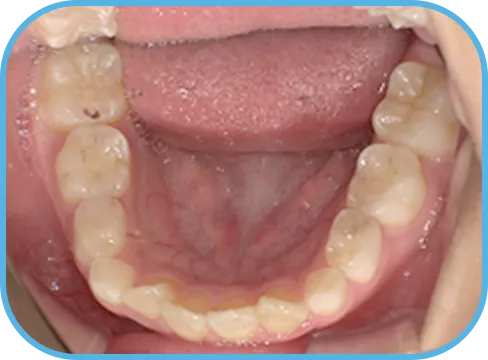

• 下 顎

治療前下顎からの歯の様子